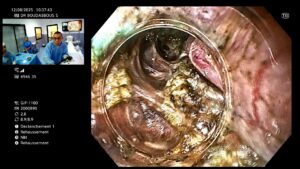

🔍 Déroulement de la procédure

- Réalisée sous anesthésie générale.

- Un endoscope flexible est introduit par la bouche.

- Le médecin crée un tunnel sous la muqueuse œsophagienne.

- Il sectionne les fibres musculaires du SIO responsables de l’obstruction.

- Le tunnel est refermé avec des clips endoscopiques.